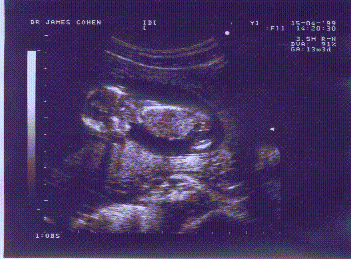

ec1.gifec2.gif

ou bien tous les deux sur la même photo, avec le sourire svp !

ec3.gif